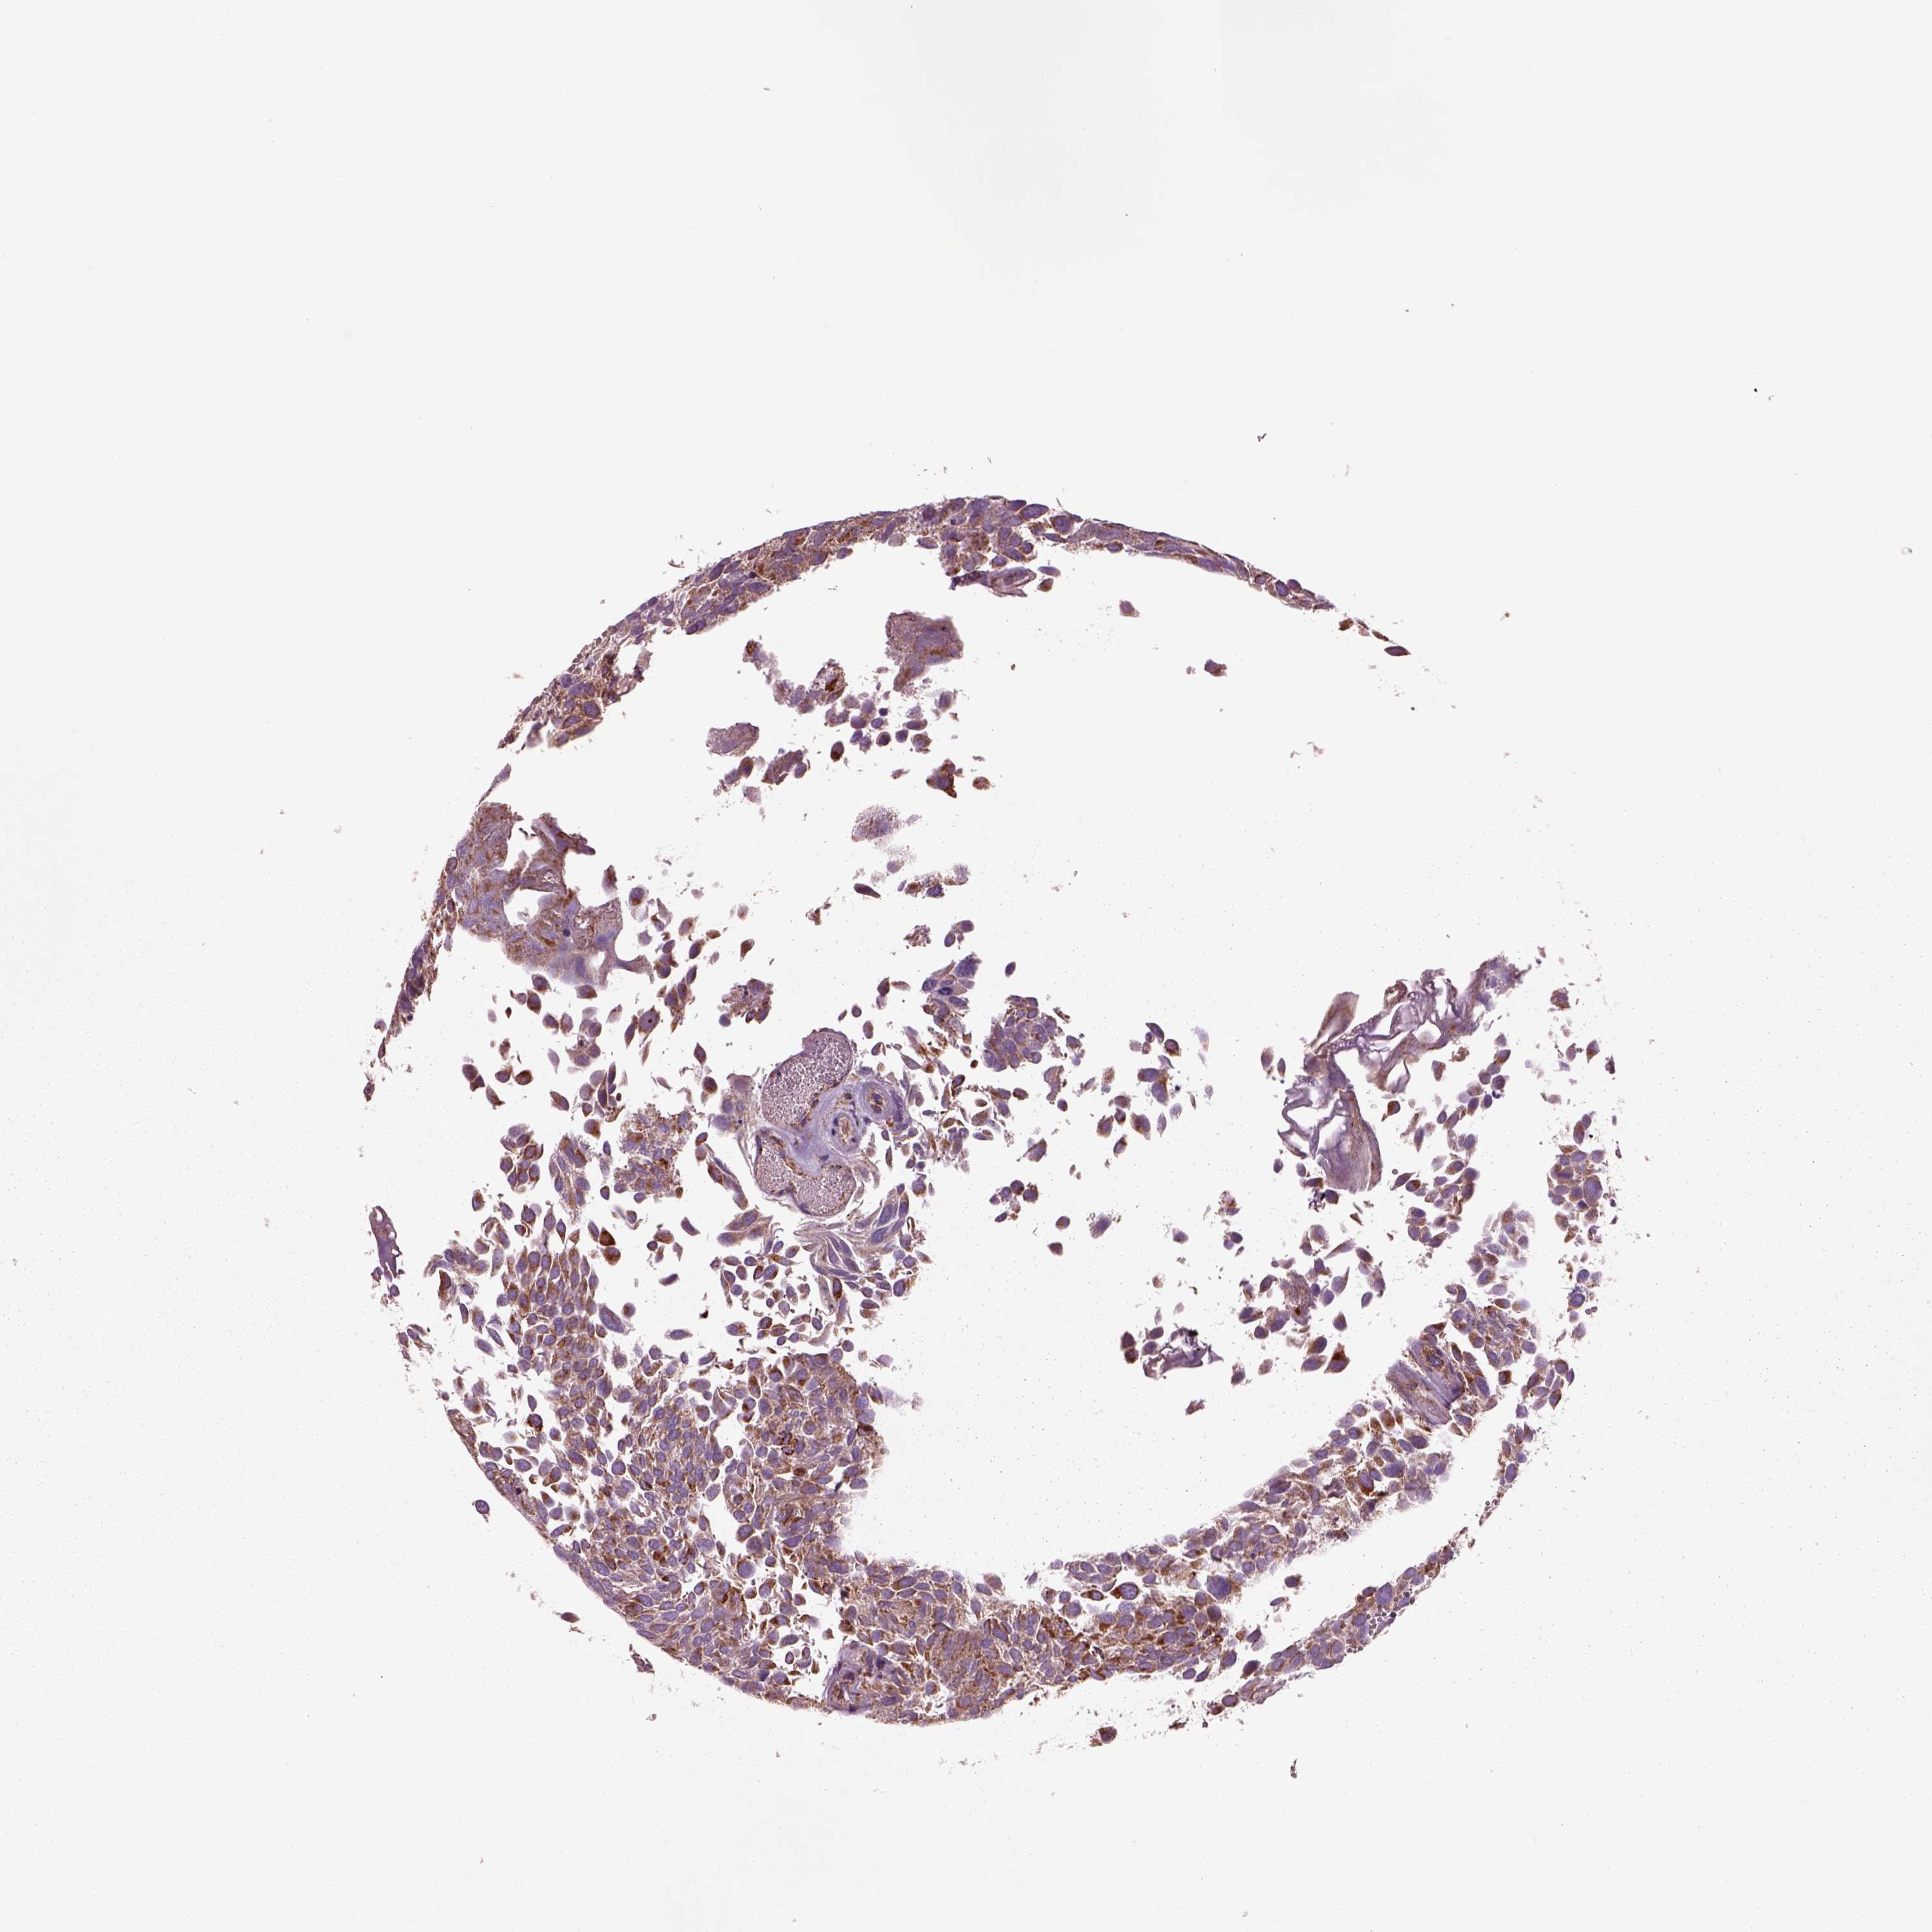

UROTHELIAL CANCER - Protein expressioni

A mouse-over function shows sample information and annotation data. Click on an image to view it in a full screen mode. Samples can be filtered based on level of antibody staining by selecting one or several of the following categories: high, medium, low and not detected. The assay and annotation is described here.

Note that samples used for immunohistochemistry by the Human Protein Atlas do not correspond to samples in the TCGA dataset.

Antibody stainingi

Antibody staining in the annotated cell types in the current human tissue is reported as not detected, low, medium, or high, based on conventional immunohistochemistry profiling in selected tissues. This score is based on the combination of the staining intensity and fraction of stained cells.

Each image is clickable and will lead to virtual microscopy that enables deeper exploration of all samples and also displays staining intensity scores, fraction scores and subcellular localization as well as patient and tissue information for each sample.

Antibody HPA063636

Staining

High

Medium

Low

Not detected

Intensity

Strong

Moderate

Weak

Negative

Quantity

>75%

75%-25%

<25%

None

Location

Urothelial carcinoma, High grade

Urothelial carcinoma, NOS

Urothelial carcinoma, Low grade